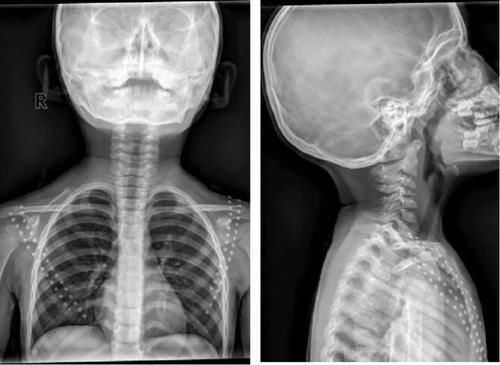

Case12:F,4y;患儿颈部活动受限1个月。